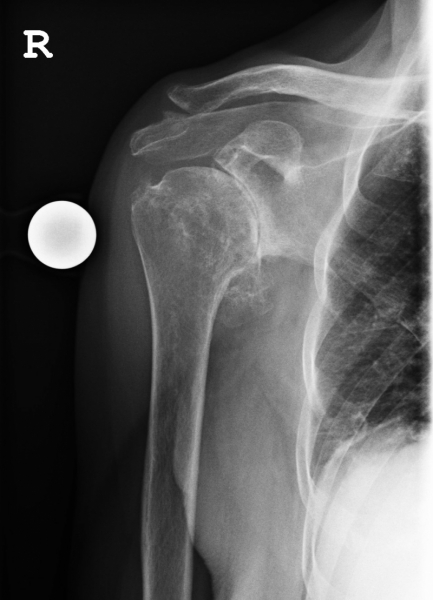

Beispiel einer Hemiprothese

Hemiprothese

Die Hemiprothese ist ein alleiniger Ersatz des Oberarmkopfes, ohne Ersatz der Gelenkpfanne.